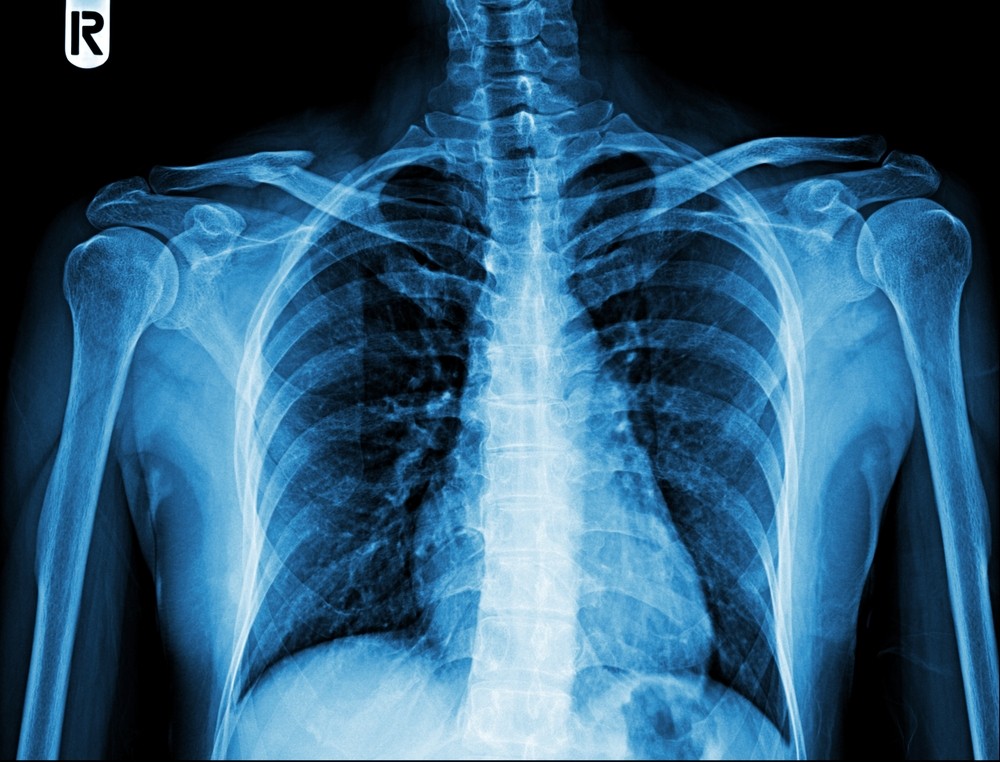

Рентген лопатки

Рентгеновское излучение наилучшим образом подходит для воссоздания структуры костной ткани на снимках, при этом отличаясь крайне низкой чувствительностью в отношении мышц, связок и хрящей. Это означает, что рентген лопатки назначается врачом в тех случаях, когда в рамках дифференциальной диагностики рассматриваются такие заболевания, как травматические и деформационные изменения (переломы, вывихи, трещины, подвывихи), очаги воспаления и некроза, новообразования злокачественного и доброкачественного типа, а также наличие инородных тел в зоне плечевого пояса.